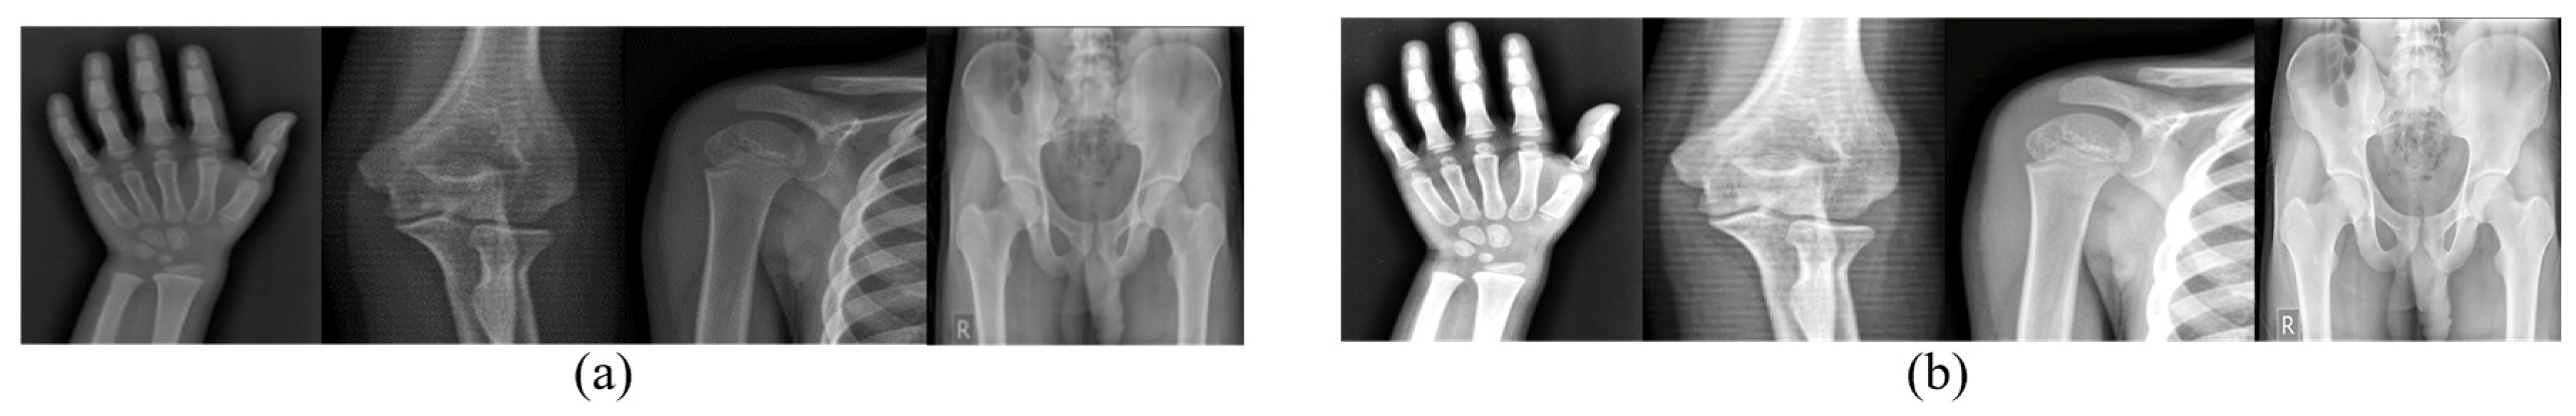

3.1. Preprocessing

4.1. Dataset